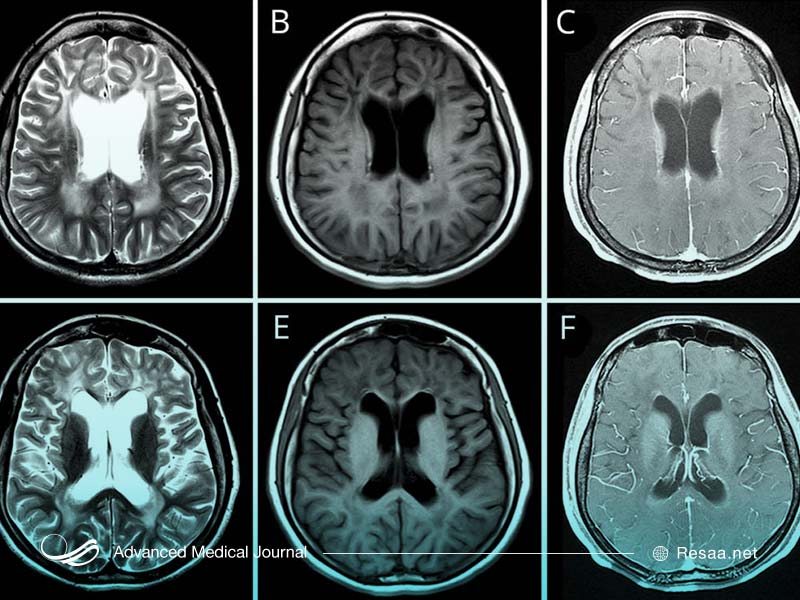

- هیدروسفالی “hydrocephalus” (مایعات اضافی در مغز)

- مغز بزرگ شده

اغلب پزشکان براساس علائم ارائه شده به بیماری الكساندر مشكوك میشوند. سپس آنها نمونه خون گرفته و به منظور انجام آزمایش ژنتیک، آن را ارسال میکنند. در بیشتر موارد و به طور معمول آزمایش خون، شامل تمام مواردی است که پزشکان به منظور تشخیص بیماری به آن نیاز دارند.

با استفاده از جراحی میتوان تا حدی هیدروسفالی را تسکین داد. این جراحی شامل قرار دادن شانت “shunt” به منظور تخلیه مایعات در مغز و تخلیه فشار بر روی مغز است.